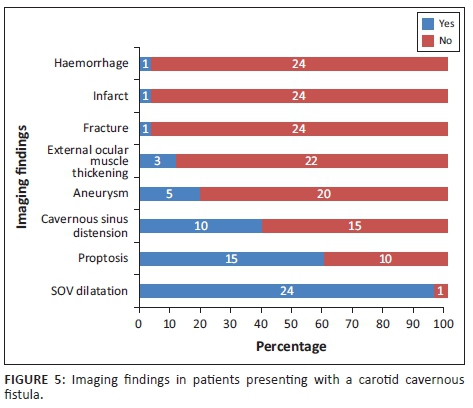

The imaging findings for the 25 patients with imaging data are presented in Figure 5. The most common finding was dilatation of the superior ophthalmic vein (96%) followed by proptosis (60%) and cavernous sinus distension (40%).

A dilated superior ophthalmic vein is often the initial finding on imaging and was found in 96% of the reviewed image data in our study, which compared favourably to other reports of 86% - 100% on enhanced CT and 75% - 100% on T1W or post-contrast MRI.4 Other findings on axial imaging include proptosis, retrobulbar fat stranding, sinus distension and early/avid enhancement of the affected CS (see Figures 7 and 9). In addition, CT allows easier identification of fractures and complications such as haemorrhage, whereas MRI allows the detection of abnormal flow voids within the CS. Magnetic resonance is understood to be superior to CT in detection of subtle signs.4